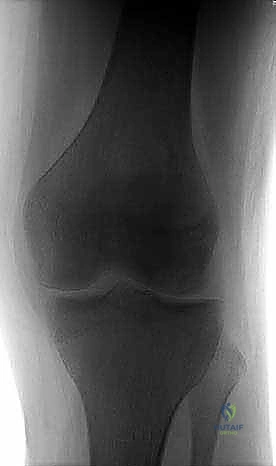

2. التصوير بالأشعة السينية (X-rays)

هي الخطوة التصويرية الأولى والأساسية. يطلب الدكتور هطيف صوراً بوضعيات محددة (أمامية خلفية، جانبية، وضعية النفق Notch view، ووضعية شروق الشمس Skyline view) أثناء الوقوف (تحميل الوزن). تساعد الأشعة السينية في رؤية العيوب العظمية، وتحديد حجم الآفة، واكتشاف أي أجسام حرة (Loose bodies) متكلسة داخل المفصل.